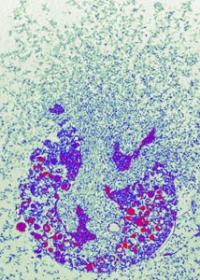

image: Fig. 1: Neutrophil granulocytes have trapped Shigella bacteria in NETs. view more

Credit: Dr. Volker Brinkmann, Max Planck Institute for Infection Biology

The group of scientists lead by Arturo Zychlinsky at the Max-Planck-Institute for Infectious Biology discovered a second killing mechanism: neutrophil granulocytes can form web-like structures outside the cells composed of nucleic acid and enzymes which catch bacteria and kill them. The scientists were able to generate impressive micrographs of these nets. But it remained a mystery how the granulocytes could mobilise the contents of their nuclei and catapult it out of the cells.